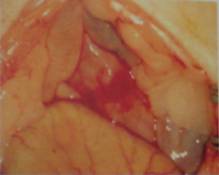

Laparotomia, prin incizie mediana posterioara s-a realizat respectând regulile de asepsie. Prin retractie, s-a obtinut o buna expunere a organelor abdominale, umezindu-se repetat cavitatea peritoneala cu solutie CIN la 0,9% (în total între 3-5 ml) (vezi Fig. 1).

Figura 1 - Aspect anatomic normal al organelor din cavitatea abdominala de soarece (Wistar)